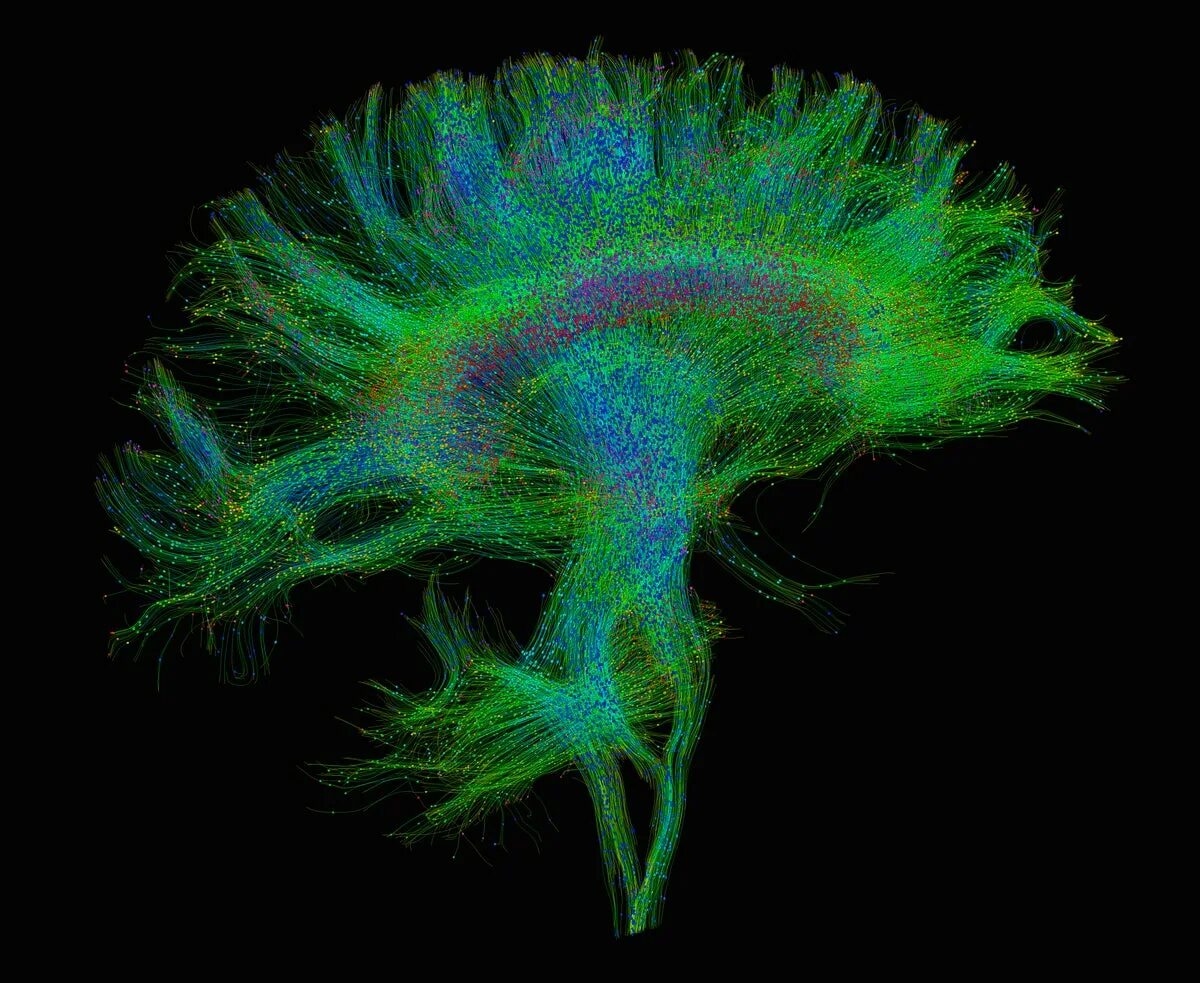

Diffusion tensor